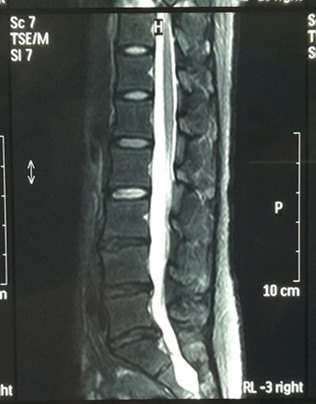

骨科的病人都要給醫(yī)生提供片子(影像學(xué)資料),如果能夠盡快提供合格的片子,有助于醫(yī)生盡快提供檢查和治療的建議。那么如何更好的提供合適的片子呢? 現(xiàn)在大家手里的手機(jī)都有非常好的照相功能,把手里的片子(核磁共振、CT片、X光片)放在白屏的電腦或者電視機(jī)上,當(dāng)然最好是在醫(yī)院專門的閱片燈上就更好了,都可以拍攝非常清楚的片子給醫(yī)生。拍片子的時(shí)候,大家要拍清楚細(xì)節(jié)的部分,醫(yī)生才能夠給出準(zhǔn)確的答復(fù)。否則,你糊弄醫(yī)生,醫(yī)生無法給你一個(gè)肯定的答復(fù)。 大家盡量上傳這樣的單幀照片,方便醫(yī)生準(zhǔn)備判斷病情。不要怕麻煩,為了您的病情,辛苦一點(diǎn)。 下點(diǎn)評(píng)患者的照片,供大家參考。 第一個(gè) 合格的片子,120KB。 照相方法:放在白天的窗戶玻璃上,適合家庭拍照的方法。可以看出做檢查的單位,說明照相的方法正確。提供了2張核磁共振矢狀位和水平位的照片,照相機(jī)的鏡頭位置正確,是一個(gè)有拍照經(jīng)驗(yàn)的攝影者的照片。許多病友拍出來的是斜著的片子,這是初次拍片要注意的。這種圖片雖然非常好,還有可以提高的地方,比如使用各種修圖軟件,把周圍的背景裁剪掉等等。 缺陷:無法放大,辨認(rèn)患者的年齡等信息。照片沒有經(jīng)過裁剪,周圍看見了窗戶外的風(fēng)景。 報(bào)告單放置在一個(gè)黑色的背景下,字跡非常清楚。 這樣整張片子上傳,無法閱讀。請(qǐng)大家一幀一幀的拍攝并上傳。 結(jié)論:這個(gè)患者的資料比較全,但是也是看不清楚。建議:上傳原圖或者單幀拍攝 第二個(gè) 歪門斜照,無法提供幫助。 結(jié)論:這個(gè)患者的資料不全,無法提供幫助。 第三個(gè) 醫(yī)生是如何收集患者的資料拍片的? X線片、CT片和核磁共振,三種方法齊全,是一個(gè)術(shù)前患者的合格的資料??梢詾獒t(yī)生提供治療、科研、教學(xué)使用的資料。 技術(shù)指標(biāo):這些照片的高度統(tǒng)一選擇了400像素(pixel)。文件的大小為40KB。 點(diǎn)評(píng):患者提供的照片可以使用大一點(diǎn)的像素,比如高度使用800-1000像素都可以的。文件的大小在50-150BK都是可以的。有助于醫(yī)生看清楚患者的信息。如果患者在什么地方住過院,能提供一個(gè)簡(jiǎn)單的病例,更有助于醫(yī)生的判斷。 影像學(xué)資料統(tǒng)一使用了黑白模式。照片鏡頭位置好,周圍的字跡分辨非常清楚。有大片,也有重點(diǎn)部位的小片的大模式。有助于看請(qǐng)清楚患者的整體病情和具體病情。能提供類似的影像學(xué)資料是最好的。 X線片:對(duì)觀察患者腰部整體的信息非常重要。 側(cè)位片 CT片對(duì)觀察患者的突出是否有骨化非常重要,同時(shí)周圍的字跡要清楚。 核磁共振有整體片,有重點(diǎn)片,非常有助于確定診斷和確定治療的方法。 矢狀位的中心片。 通過椎間盤的水平位,非常重要。 最好提供一個(gè)住院病例,最差提供一個(gè)門診病例也好。 包括:一、主訴: 二、病例特點(diǎn): 1、現(xiàn)病史: 2、??魄闆r: 3、輔助檢查: 三、初步診斷: 還有一個(gè)方法:使用電腦,打開OFFICE里面的做幻燈的powerpoint軟件,做一個(gè)空白的PPT,然后打開全屏。電腦即可顯示一個(gè)白屏,調(diào)整到最大的亮度。放上原片子即可拍出合格的片子到手機(jī)。 最后醫(yī)生和患者一起努力,獲得一個(gè)良好的治療結(jié)果。 患者請(qǐng)?jiān)诰W(wǎng)站上傳JPG格式的照片即可,但注意要傳原圖,不能使用壓縮文件,或者直接微信傳原圖。